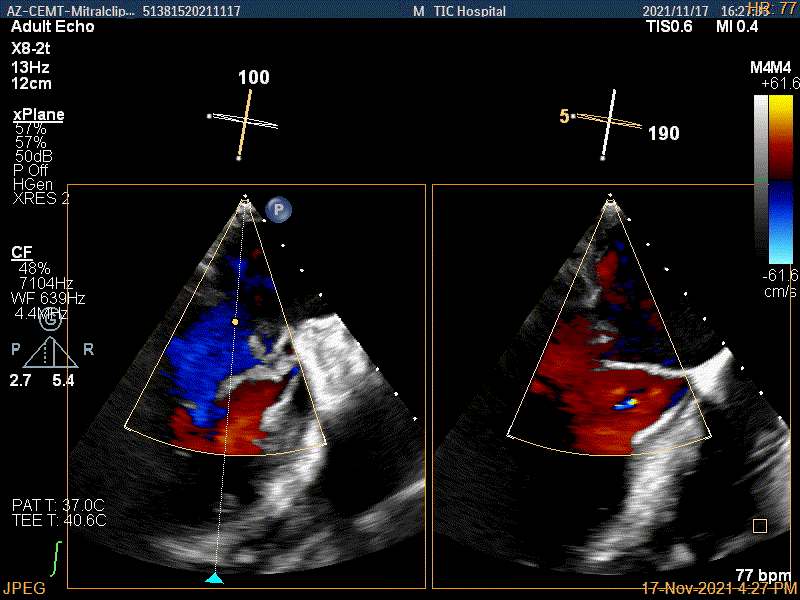

Multivue视图下将夹子正对AC区并调节Rotate

X-plane:下夹子尝试捕获靠近AC区脱垂瓣叶

3D证实夹子内侧残余脱垂(P1区)

3Dcolor证实残余分流主要来源于残余脱垂